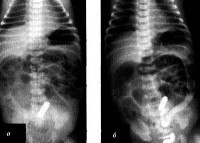

Для подтверждения кишечной непроходимости применяется рентгенография с контрастированием. Данное исследование свидетельствует о множественных растяжениях петель тонкого кишечника, изредка - о наличии горизонтального уровня жидкости. Диагностическим критерием мекониального илеуса является симптом «мыльных пузырей» в правой подвздошной области, обусловленный смешиванием мекониальных масс с пузырьками воздуха. При наличии перитонита обнаруживаются участки обызвествления по всей брюшной полости - от пространства под куполами диафрагмы до полости малого таза.